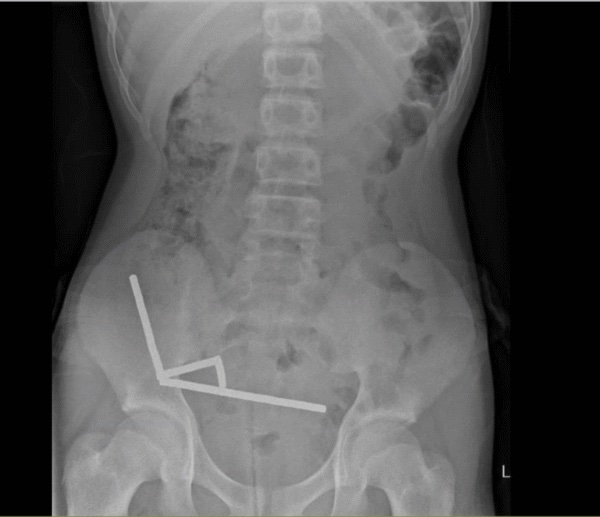

Using an X-ray, doctors imaged four linear chains in separate parts of the boy’s bowel.

X-ray showing the magnet chains in the abdomen of the New Zealand teen. (Lekamalage et al., NZMJ, 2025)

During surgery, the chains were found in separate sections of the small bowel and caecum. Squeezing together, they were causing several patches of tissue to die from a lack of blood in what is known as pressure necrosis.